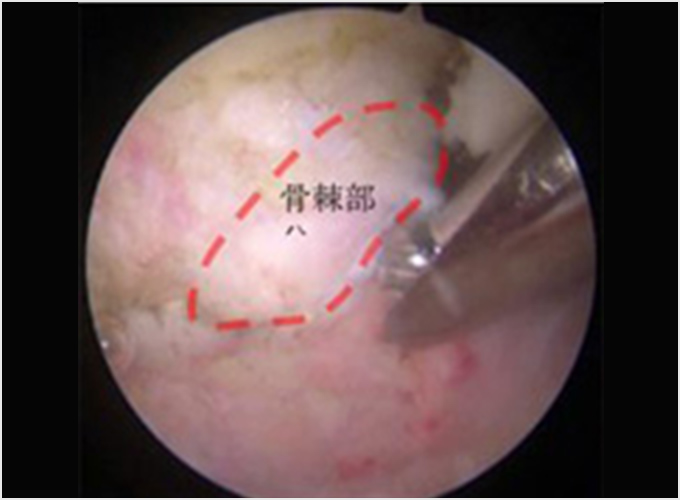

肘頭骨棘骨折

投球を繰り返すことで少しずつ骨に棘(とげ)のような余分な骨ができてくることがあります。これを骨棘(こつきょく)といいます(図7a)。投球で肘が伸びたときに、肘の後ろで骨同士の衝突が起こり、骨棘が骨折します。投球を休止し、フォームや体の硬さなどの問題を改善したりして、再発を予防します。なかなか治らない、繰り返すなどの場合には関節鏡を用いて骨のかけらや骨棘を切除する手術を行います(図7b.c)。